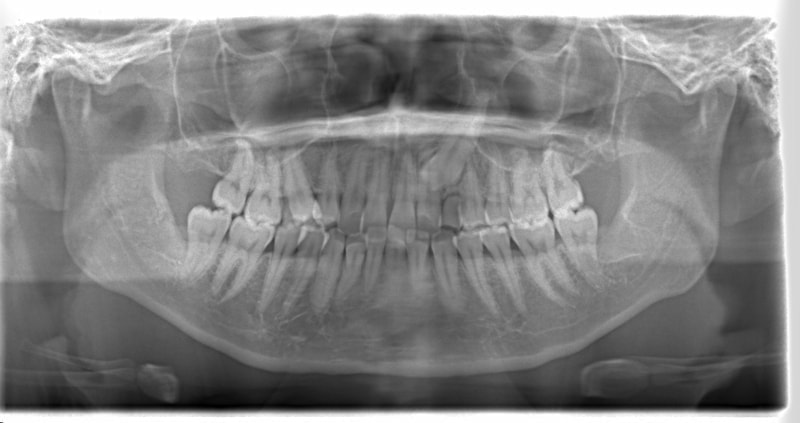

症例紹介

左上3番埋伏歯

治療法:フルパッシブブラケット:T21

治療前